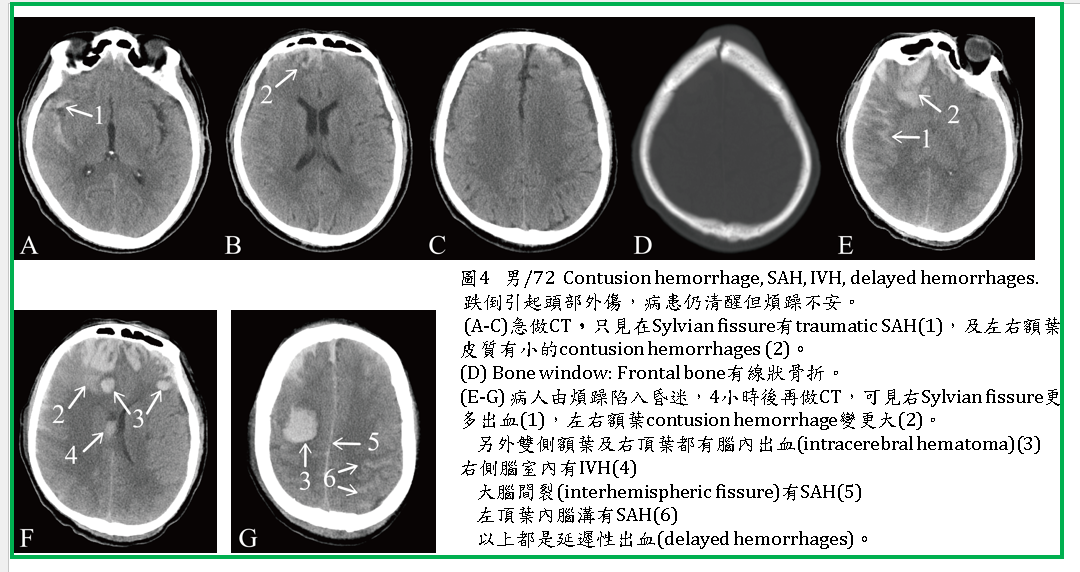

腦挫傷血塊(contusion hematoma):不合併腦水腫,這可能是腦內單獨一條血管破裂所引起(圖4) 。

1. 有些挫傷性腦出血及腦水腫,在急做CT時並未發現,或範圍較小,但會有延遲性出血及腦水腫(delayed hemorrhage and edema) (圖4 ) ,因此當病患臨床症狀有變化時應再做CT。

2. 腦挫傷常常合併SDH、EDH(圖1),也常合併SAH (圖3,4,5,6)、IVH 。